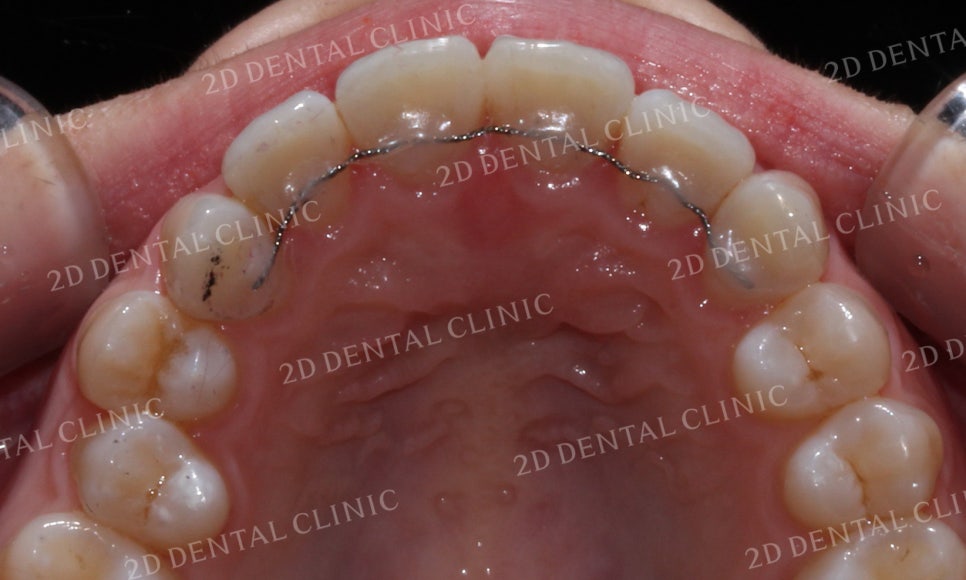

전치를 자세히 살펴보면

상악의 공간이 좁아 치아들이

고르게 배열되지 못한 모습이었습니다.

덧니교정 후 부족했던 상악의 공간이

조금씩 확보되면서 가지런한 치열을 되찾은 모습이네요!

이번 덧니Case의 경우 발치과정 없이

교정을 진행하였습니다.

따라서 치아가 올바르게 배열되기 위해

발치 교정보다 비교적 많은 시간이 소요되었는데요,

만약 치열이 심하게 흐트러진 경우

비발치로 교정을 진행하지 못할 수 있기 때문에

교정 전 치과에 방문하시어 반드시

정밀검진을 받아보시기 바랍니다.

투디교정의 경우 설측에 브라켓이 부착되기 때문에

교정장치의 노출을 꺼리시거나 미관상 문제 등으로

교정을 고민하시는 환자분들께 적합한 교정 방식입니다.